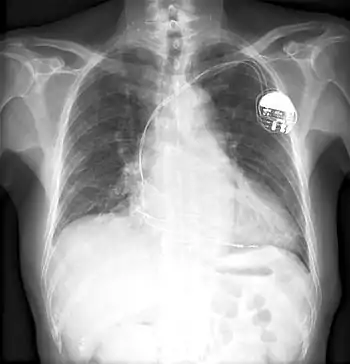

Other notable inventions include a variable resistor used in guided missiles.[15] His most famous invention was likely a control unit for the artificial cardiac pacemaker.[4] The device essentially uses electrical impulses to maintain a regular heartbeat. Among his other inventions is a burglar-proof cash register.[16]